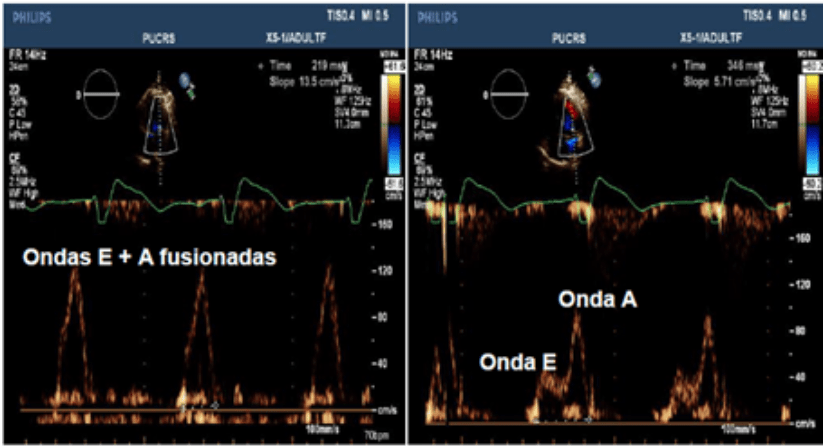

Andrés Di Leoni Ferrari MD, PhD1, José Plutarco Gutiérrez Yanez MD.2 1Coordenador da Unidade de Estimulação Cardíaca do Hospital São Lucas da PUCRS – Porto Alegre. 2Fellow em Eletrofisiologia do Hospital São Lucas da PUCRS. [Descargar PDF] En este artículo el Dr...

Emilio Logarzo 1,2, Daniel Ortega1,2, Luis Barja1,2, Analía Paolucci 1,2, Gerson Revollo 2, Juan Manuel Aboy 2, Nicolás Mangani 1,2 1Clínica San Camilo. 2 F.I.B.A. [Descargar PDF] Resumen. La estimulación del ventrículo derecho genera un bloqueo completo de rama...